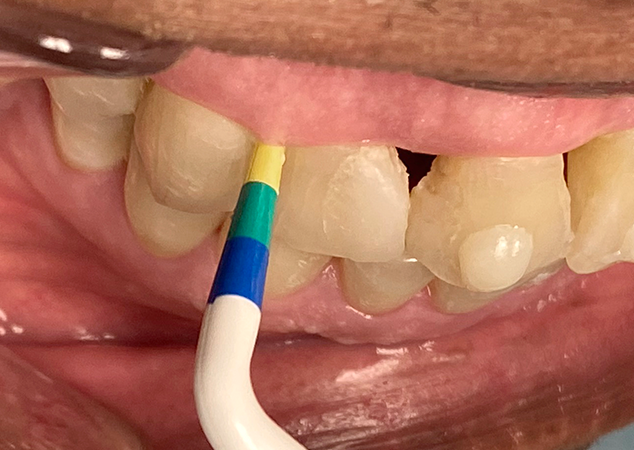

Lors de la consultation initiale, il est important de mesurer les embrasures gingivales à l'aide de la jauge de triangle noir Bioclear (Fig. 4). Ensuite, effectuez un essai de matrice pour évaluer l'exactitude de la mesure et la sélection ultérieure de la matrice destinée à combler l'embrasure (Fig. 5). L'expérience du clinicien et un œil attentif à l'esthétique guident la sélection finale de la matrice la mieux adaptée pour recréer le profil d'émergence approprié. Dans ce cas, nous avons convenu avec le patient de combler les embrasures de 13 à 23 et d'utiliser des matrices de triangle noir Bioclear pour réaliser des facettes à 360° afin de remodeler et de reconstruire les profils faciaux et incisaux.

FIG. 4A

FIG. 4B

FIG. 4C

Lors de la consultation initiale, la correspondance des teintes est obtenue à l'aide de pastilles de composite placées et polymérisées sur la surface vestibulaire des incisives centrales. Chaque embrasure est mesurée et enregistrée à l'aide de la jauge à triangle noir Bioclear.